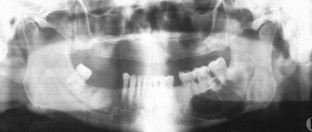

Fig. 1